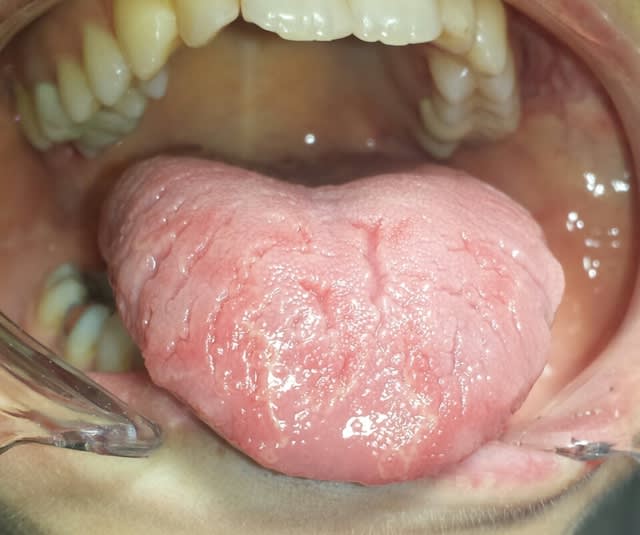

langue géographique aussi.. pour éviter l'apparition de lésion, limiter aliments acides au max..

sinon pas de traitement particulier..

Si pas de douleurs, rien à faire (notamment au niveau "esthétique"), la langue géographique est quasiment considérée comme une variation physiologique.